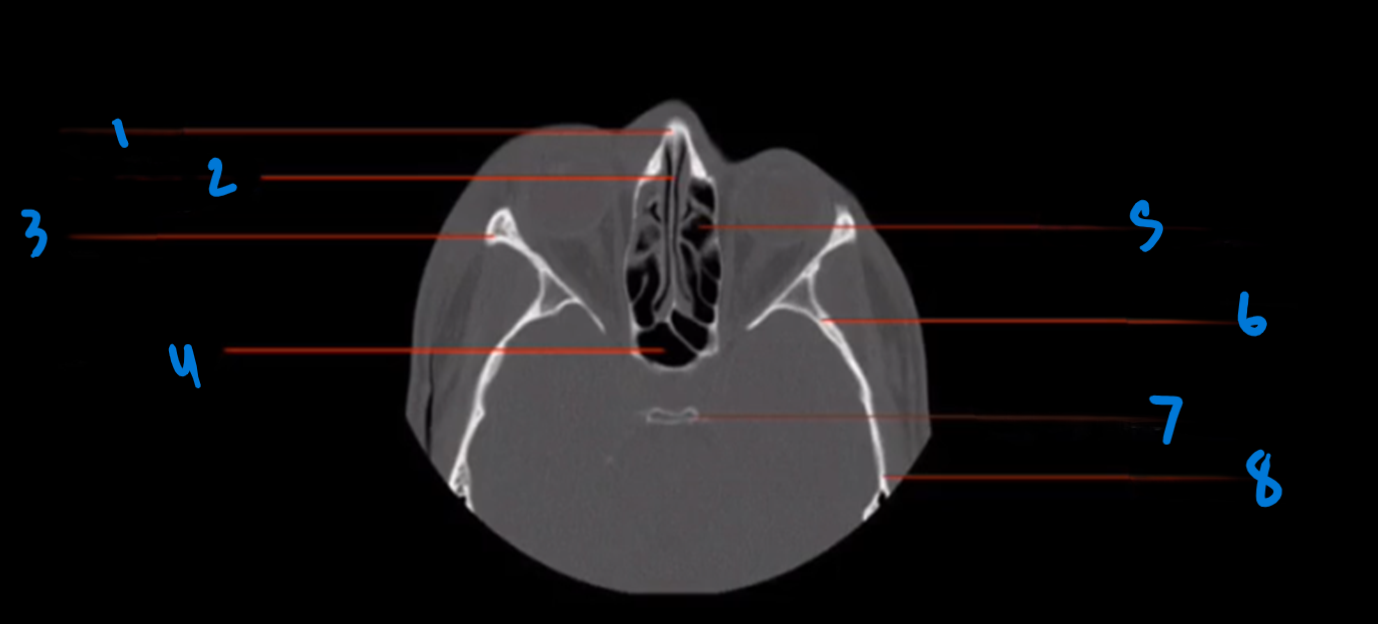

What is the landmark #1 called?

Nasal septum

What is landmark # 2 called?

Zygoma

What is landmark # 3 called?

Maxillary Sinus

WHat is landmark # 4 called?

Sphenoid Bone

What is landmark # 5 called?

Carotid Canal

Nasal bone

What is landmark # 6 called?

Maxillary Bone

WHat is landmark # 7 called?

Sphenoid Sinus

What is landmark # 8 called?

Mastoid air cells, Temporal bone